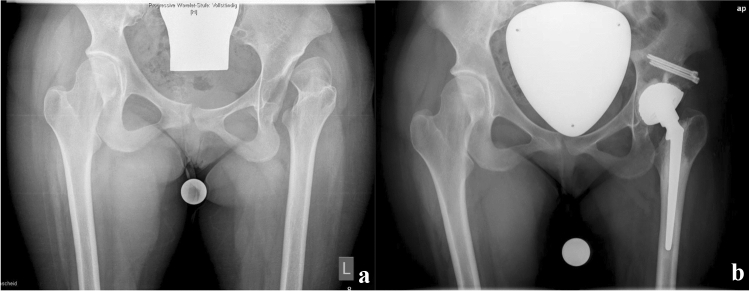

The THA (exemplary Fig. 1a, b) were executed through a lateral approach. In one patient with a painful chronic dislocation a cemented dysplastic hip stem (CDH stem, Implantcast GmbH, Buxtehude, Germany) with a dual-mobility cemented acetabular cup (Ecofit 2M, Implantcast GmbH, Buxtehude, Germany) was used and was combined with acetabular augmentation using the femoral head [17]. The other three cases were not dislocated and were addressed using a small cementless stem with diaphyseal anchorage (Dialoc, Implantcast GmbH, Buxtehude, Germany) and a cementless porous coated shell with additional screw fixation on the acetabular side (Trident, Stryker Corp., Kalamazoo, MI, USA). All patients underwent extensive arthrolysis and tenotomies to facilitate the joint replacement surgery and to treat contractures.

Fig. 1.

a Preoperative radiograph showing chronic hip dislocation on the left with osteoarthritic changes. b Postoperative radiograph after THA and concomitant acetabular augmentation with the femoral head